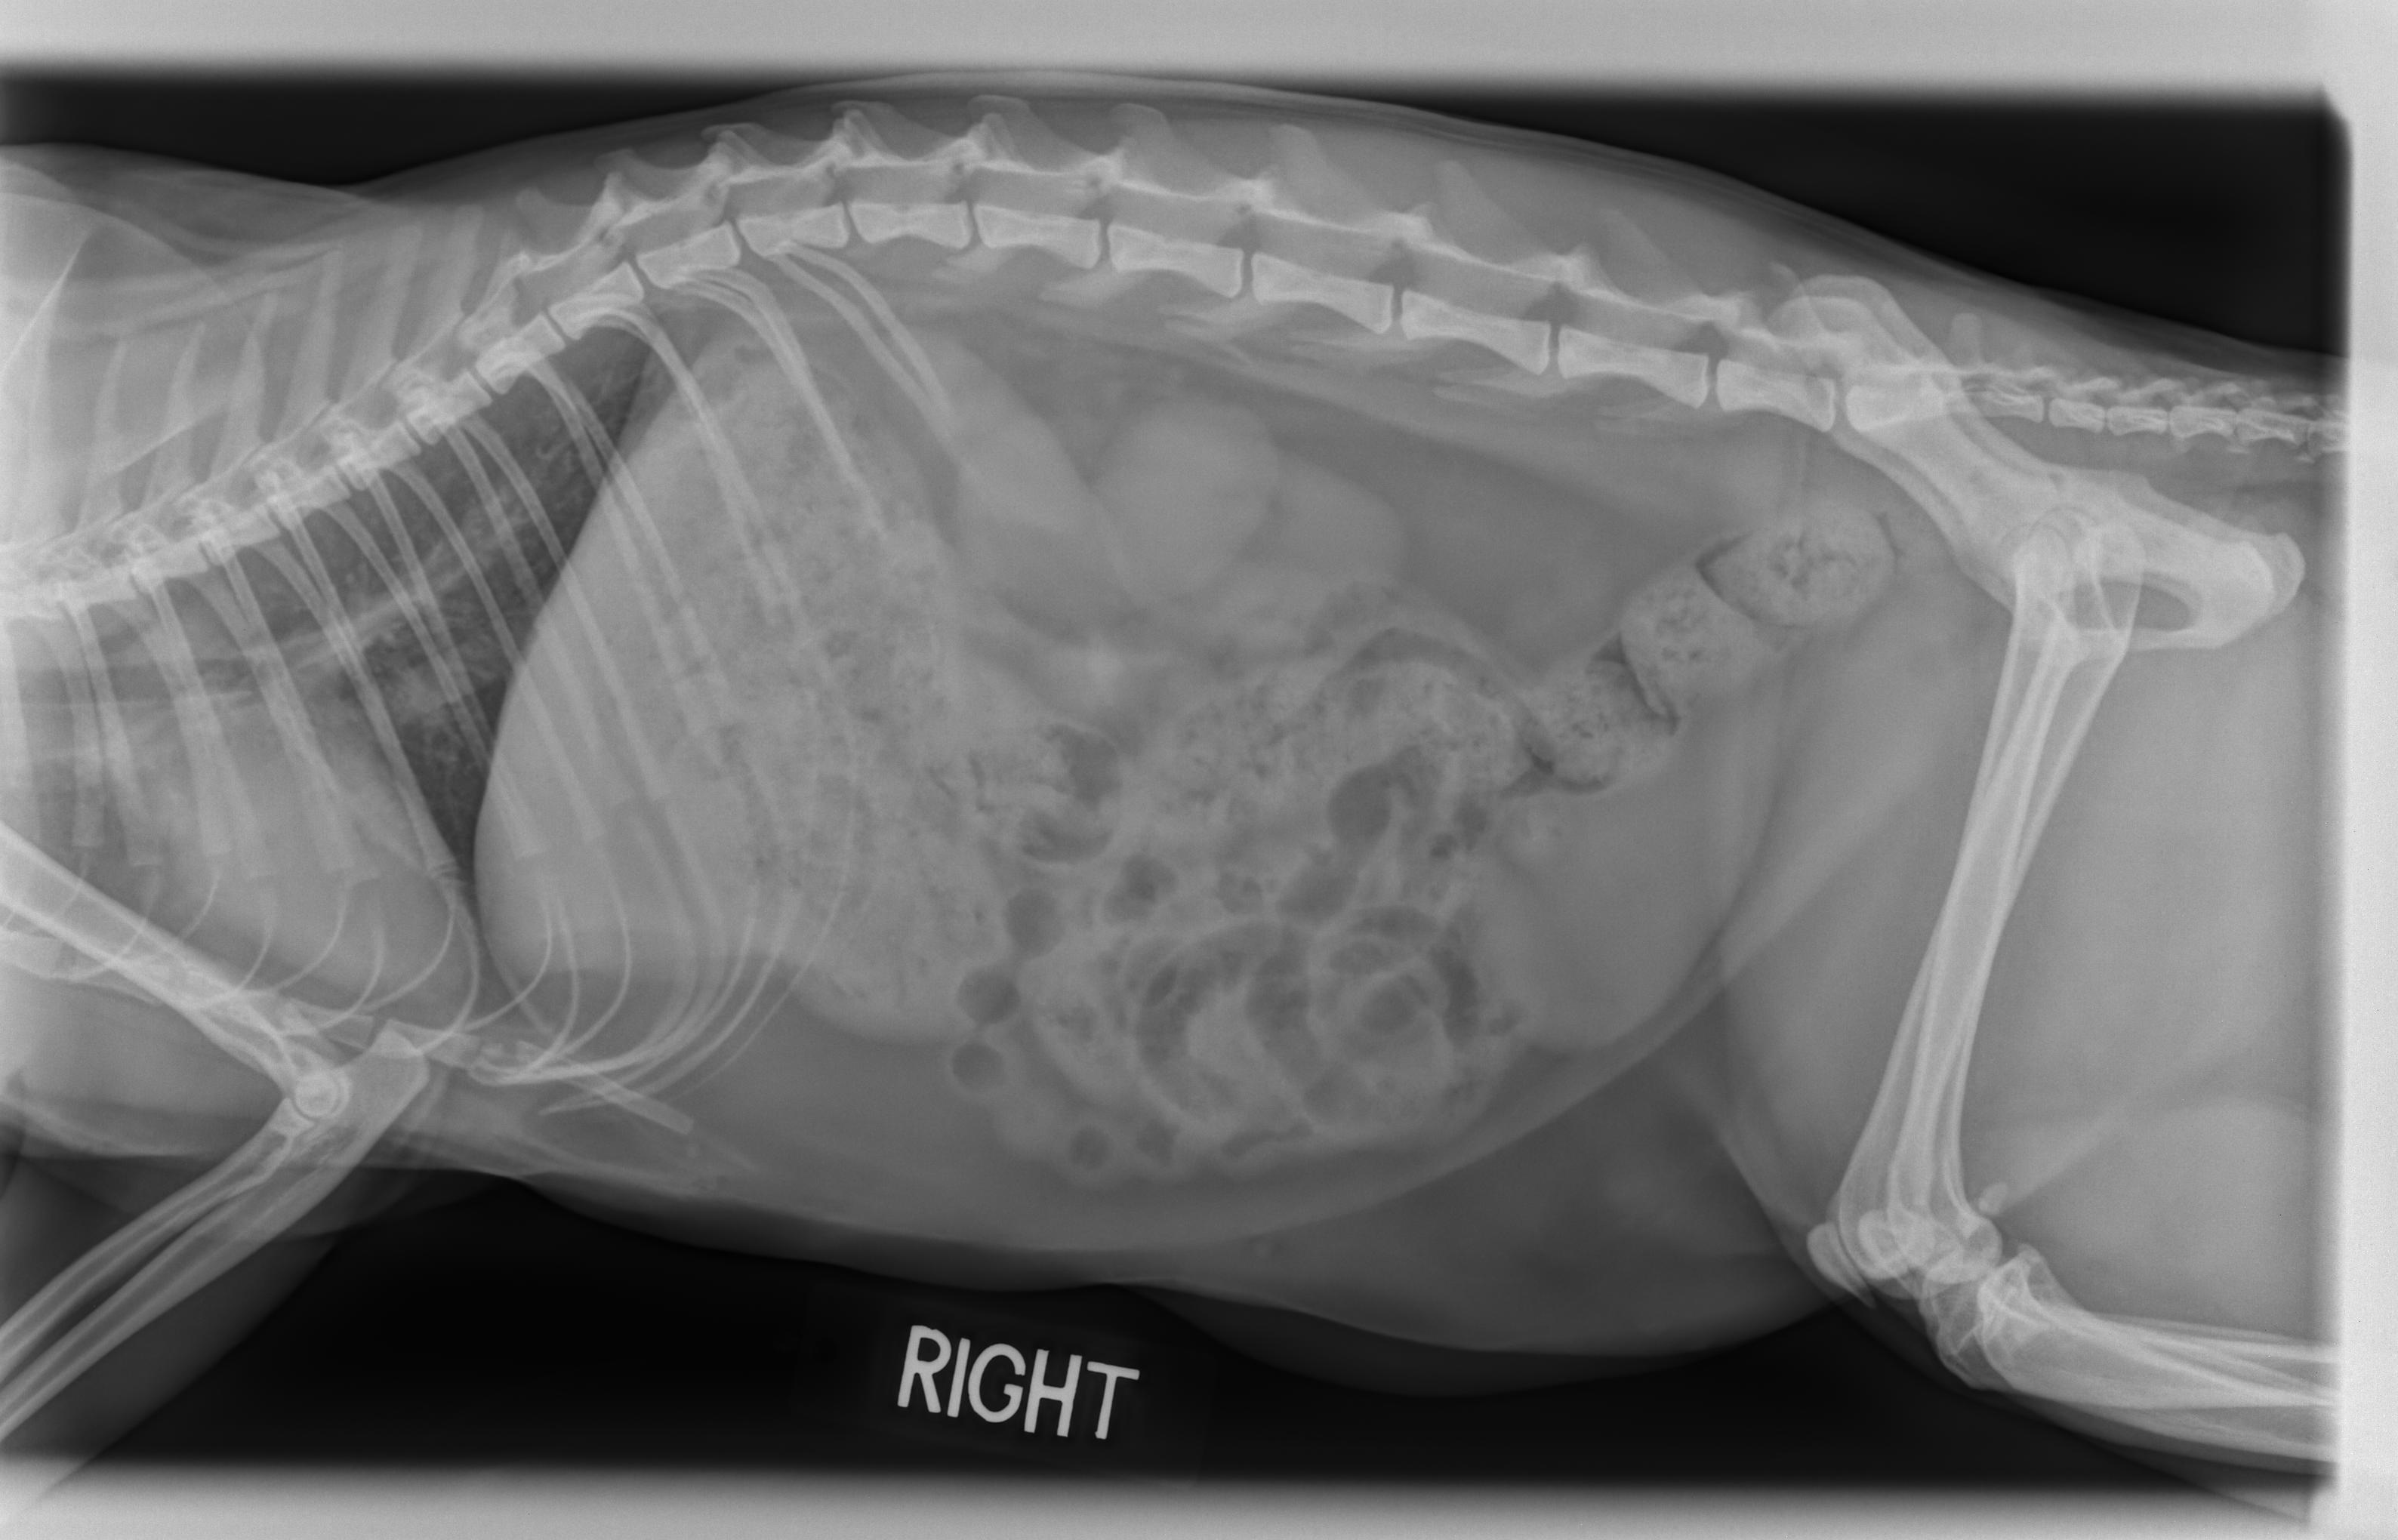

Using this technology, our veterinarian can assess internal organs such as the heart, lungs, liver and kidneys for disease and conditions such as pneumonia. Additionally, digital radiography is used to inspect areas such as the abdomen and the intestinal tract for foreign objects and obstructions, to detect masses and discover pregnancies. Our doctor can also determine the severity of orthopedic injuries such as breaks and fractures, diagnose chronic arthritis, and certain spinal cord diseases.

Digital radiography provides images much faster and with greater clarity than traditional x-rays. The digital images can be manipulated, enhanced, and contrasted, enabling us to diagnose a condition more accurately.